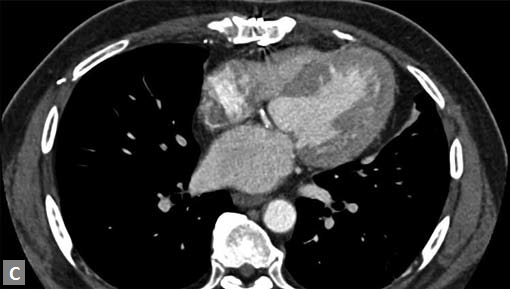

Filling defects (Figs 16A and B) may be seen in main

pulmonary artery (MPA), left pulmonary artery (LPA) and

right pulmonary artery (RPA), interlobar artery, segmental

divisions (Figs 17A and B). On occasions, detection in distal

parts of segmental divisions is difficult. This can be further

confounded by motion artifacts, non- or minimally opacified

accompanying pulmonary veins.